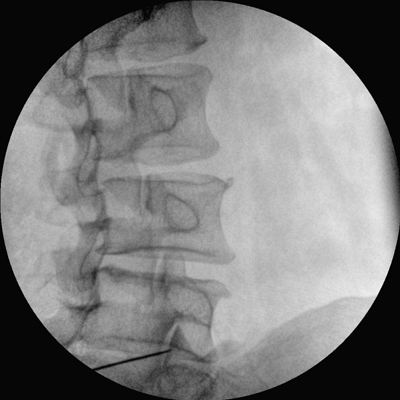

專業(yè)的圖像處理系統(tǒng),為您提供高分辨率、高灰階圖像。